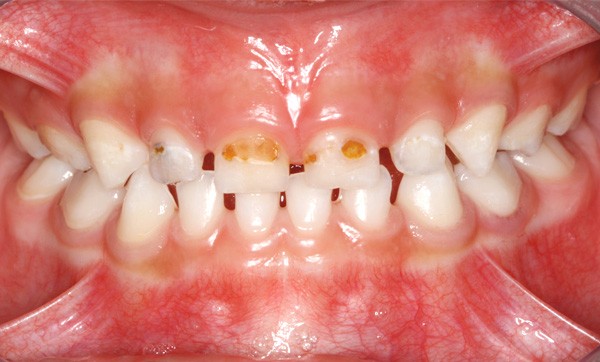

En France, la carie de la petite enfance (CPE) est souvent négligée chez l’enfant en denture temporaire, 24 % des dents temporaires affectées par des lésions carieuses cavitaires n’étant pas traitées, alors que la prévalence mondiale atteint 8,8 % [1]. Les enfants affectés ne sont souvent amenés en consultation que dans les cas sévères (tableau 1) lorsque les lésions nécessitent des réhabilitations prothétiques à envisager après correction du risque carieux (fig. 1).